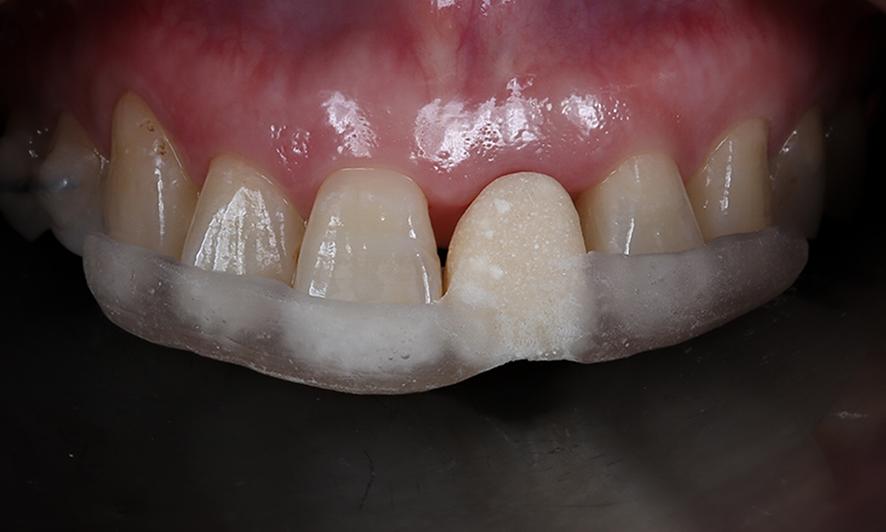

模型上のシミュレーションの通りに埋入ガイド(ステント)を製作する。

シミュレーション通りの位置にインプラントを埋入出来るようにステントと呼ばれる(透明な樹脂の部分)埋入ガイドを使い、正確性と安全性を確保しています。